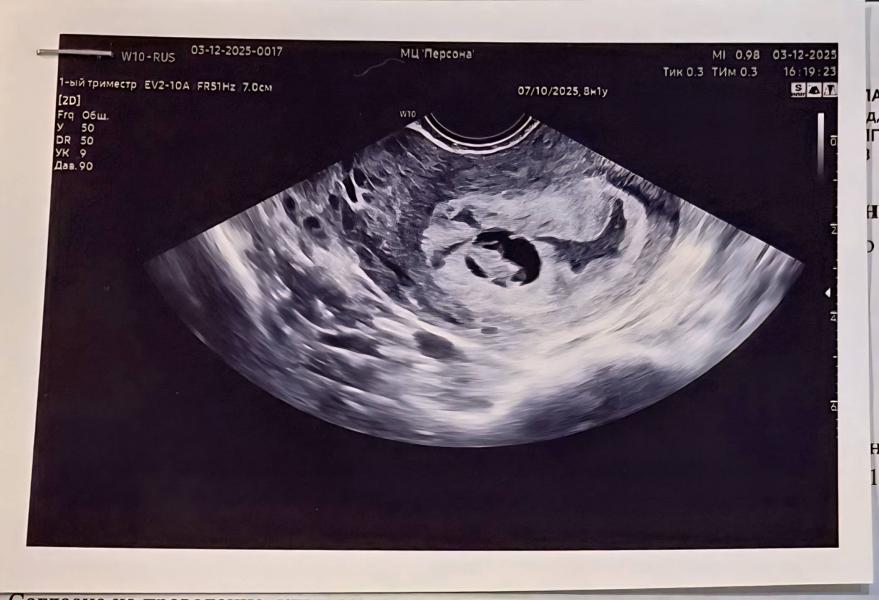

По месячным 8нед.1д., по узи 7нед.4д. Сердцебиение 172уд/мин, ктр 13,3мм.

Все хорошо. И гематома - это совсем не гематома, а полость матки) все хорошо у моего маленького новенького человека🥰